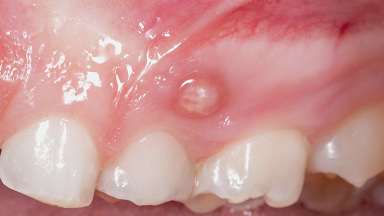

Endodontic Infection

About Root Canal Treatment

Root canal treatment may be recommended when the soft tissue inside a tooth (pulp) becomes damaged or infected, which can occur due to decay, trauma, or other causes. If left untreated, such conditions may lead to discomfort or further complications.

During the procedure, the dentist removes the affected tissue from inside the tooth, cleans and disinfects the area, and fills the space with a sealing material. In some instances, additional steps may be taken to address concerns such as tooth discolouration.

This treatment option may help retain the tooth and restore its function. Your dentist will assess your condition and discuss whether root canal therapy is appropriate in your case.